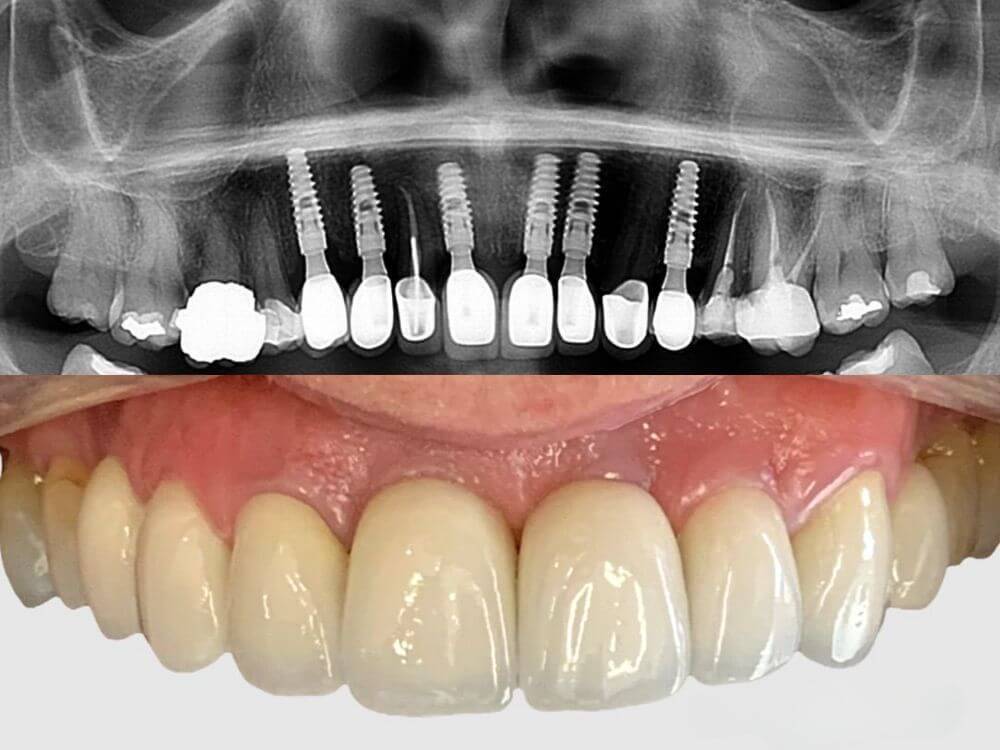

Uma prótese total fixa sobre implantes para quem perdeu todos os dentes de uma arcada. Recupera a força na mastigação e elimina desconforto ao falar e mastigar.